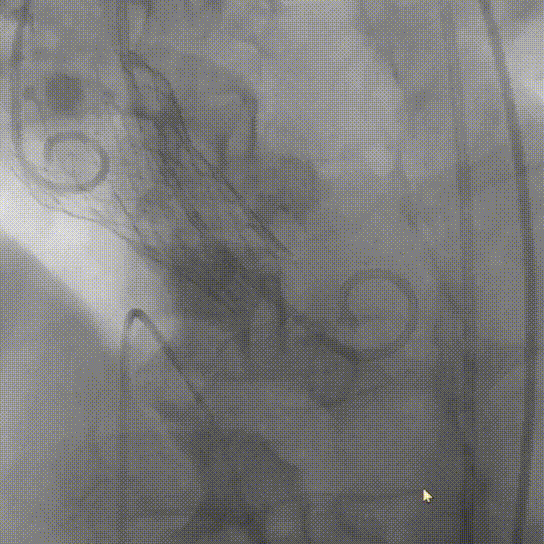

球囊预扩张

10mm*10cm小球囊预扩

23mm Z-Med预扩张

根据预扩表现决定使用26mm瓣膜